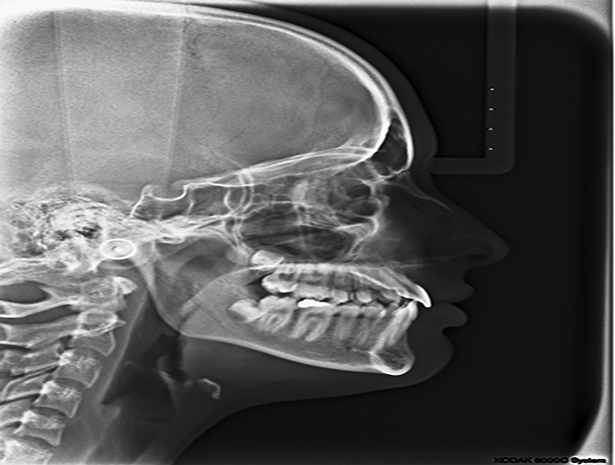

L’Ortopanoramica, infatti, oltre a mettere in evidenza i contorni dell’Anatomia dentale di entrambe le arcate del paziente, consente di valutare la quantità e il livello di altezza dell’osso che sostiene i denti, o lo stato della dentizione nei soggetti in età di sviluppo, o ancora, consente di effettuare valutazioni sull’Articolazione Temporo-Mandibolare ed i condili.

L'Ortopanoramica si chiama così perchè fatta in Ortostasi, cioè in piedi, e Panoramica perchè prende con una sola esposizione le due arcate dentarie fino ai condili. In particolare, la caratteristica forma a “ferro di cavallo” delle ossa mascellari viene ripresa in tre sezioni differenti, due laterali ed una centrale, e successivamente messa su di un'unica immagine bidimensionale e piana.